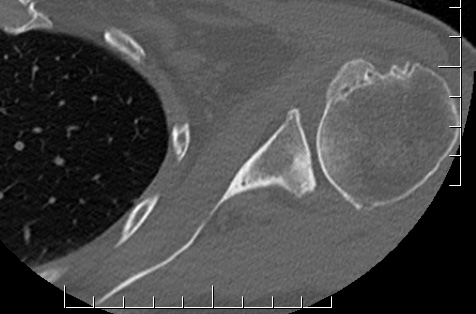

Type B - posterior subluxation of the humeral head, with biconcave glenoid and asymmetric wear

B2: biconcave glenoid with posterior rim erosion and retroverted glenoid

Type B2 glenoids

Options

1. Eccentric reaming

2. Reduce humeral head retroversion

3. Bone grafting

4. Augmented glenoids

Eccentric reaming

Limit to 10o

- compromises anterior bone stock

- risk peg penetration through vault and glenoid fracture

- associated with glenoid loosening

- excessive glenoid reaming associated with radiological loosening of glenoid